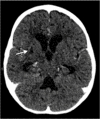

Child with tuberculous meningitis and COVID-19 coinfection complicated by extensive cerebral sinus venous thrombosis

We herein report a case of a child with tuberculous meningitis and COVID-19 coinfection complicated by hydrocephalus, arterial ischaemic stroke and extensive cerebral sinus venous thrombosis. Both conditions induce a proinflammatory cytokine drive resulting, among others, in a prothrombotic state. The disruption of the coagulation system in this case was supported by elevated D-dimers, fibrinogen and ferritin levels, consistent with thrombotic complications reported in some adult patients infected with COVID-19. The child also exhibited prolonged viral shedding that suggests severe disease.